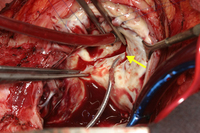

Tricuspid valve entrapped with a pacemaker lead

From the collection of Dr Thoraf M. Sundt III